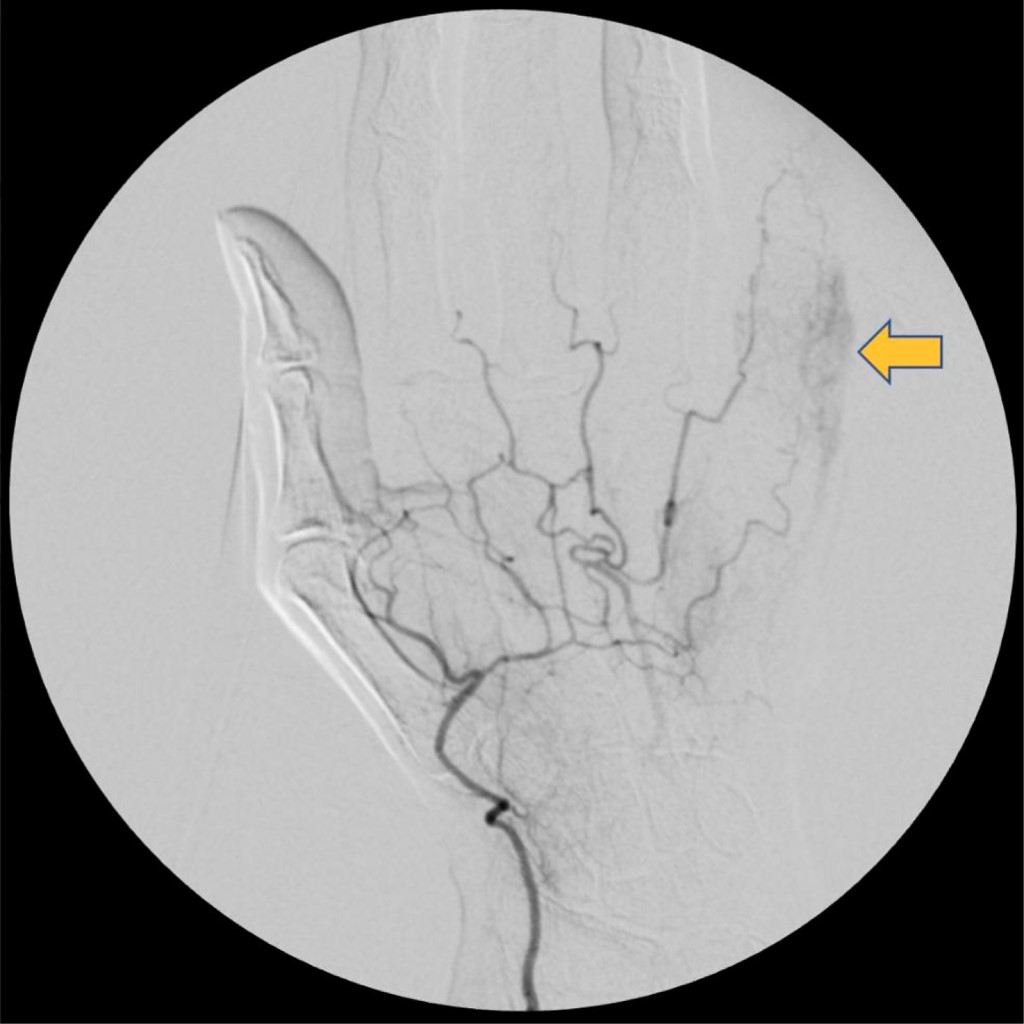

La paciente había realizado una ecografía y una angiografía que informaban la presencia de una imagen hipoecogénica de 10 × 7 mm que podría corresponder a un hematoma en la región dolorosa referida por la paciente (Figura 2). Debido a la evolución tórpida y el continuo crecimiento de la tumoración, se indicó la resección quirúrgica de la misma. El procedimiento quirúrgico fue realizado con la paciente en decúbito dorsal bajo anestesia general con su extremidad superior afectada sobre una mesa de mano. Mediante un abordaje volar de Bruner, se realizó la resección de la tumoración; se observó que la misma se encontraba en continuidad con la arteria digital colateral cubital del quinto dedo. La resección de la tumoración incluyó la excisión del segmento de la arteria digital que se encontraba en relación con la misma, ya que presentaba un daño irreparable. Posteriormente bajo magnificación microscópica se realizó lavado con heparina de ambos cabos arteriales y se realizó una arteriorrafia término-terminal de la arteria digital colateral cubital del quinto dedo mediante técnica microquirúrgica, utilizando Nylon 10-0. Posteriormente, se retiró el manguito hemostático, constatando permeabilidad de la sutura vascular. Asimismo, durante el procedimiento quirúrgico se comprobó la indemnidad del nervio colateral cubital, por lo que sólo se realizó una neurólisis del mismo (Figura 3).

Existen múltiples métodos disponibles de diagnóstico por imágenes que permiten confirmar la presencia de esta patología ante la sospecha clínica. Ellos son la ecografía Doppler, la arteriografía, la angiotomografía y la resonancia magnética.5

La ecografía Doppler es un método no invasivo que permite visualizar el flujo bidireccional de sangre a través del vaso sanguíneo, permitiendo el diagnóstico de estas lesiones.2,3,4,6,11 Es una herramienta costo efectiva que permite evaluar lesiones arteriales y es considerada el primer método de elección para el estudio de masas palpables en la mano o isquemia digital.10,11

La arteriografía es el método por imágenes más frecuentemente utilizado para demostrar y confirmar la dilatación vascular.2,4 Es considerado el "estándar de oro" para la evaluación de lesiones arteriales.10,11 Sin embargo, dado su carácter invasivo, otros métodos diagnósticos son utilizados.6 En este sentido, Lebowitz y Matzon mencionan a la angiotomografía como método alternativo para diagnóstico de lesiones arteriales con sensibilidad mayor a 95%.11 Asimismo, Bouvet y colaboradores proponen la angiotomografía como un método efectivo y fidedigno para estudiar lesiones vasculares proximales y distales.10